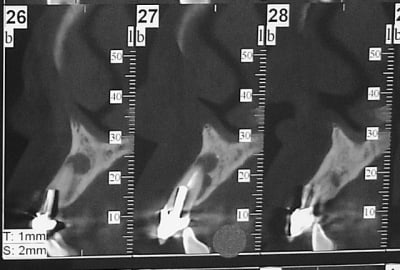

> Jolie, tu as un radio post-op ?

aussitôt demandé, aussitôt fait !!

(j+1 an)